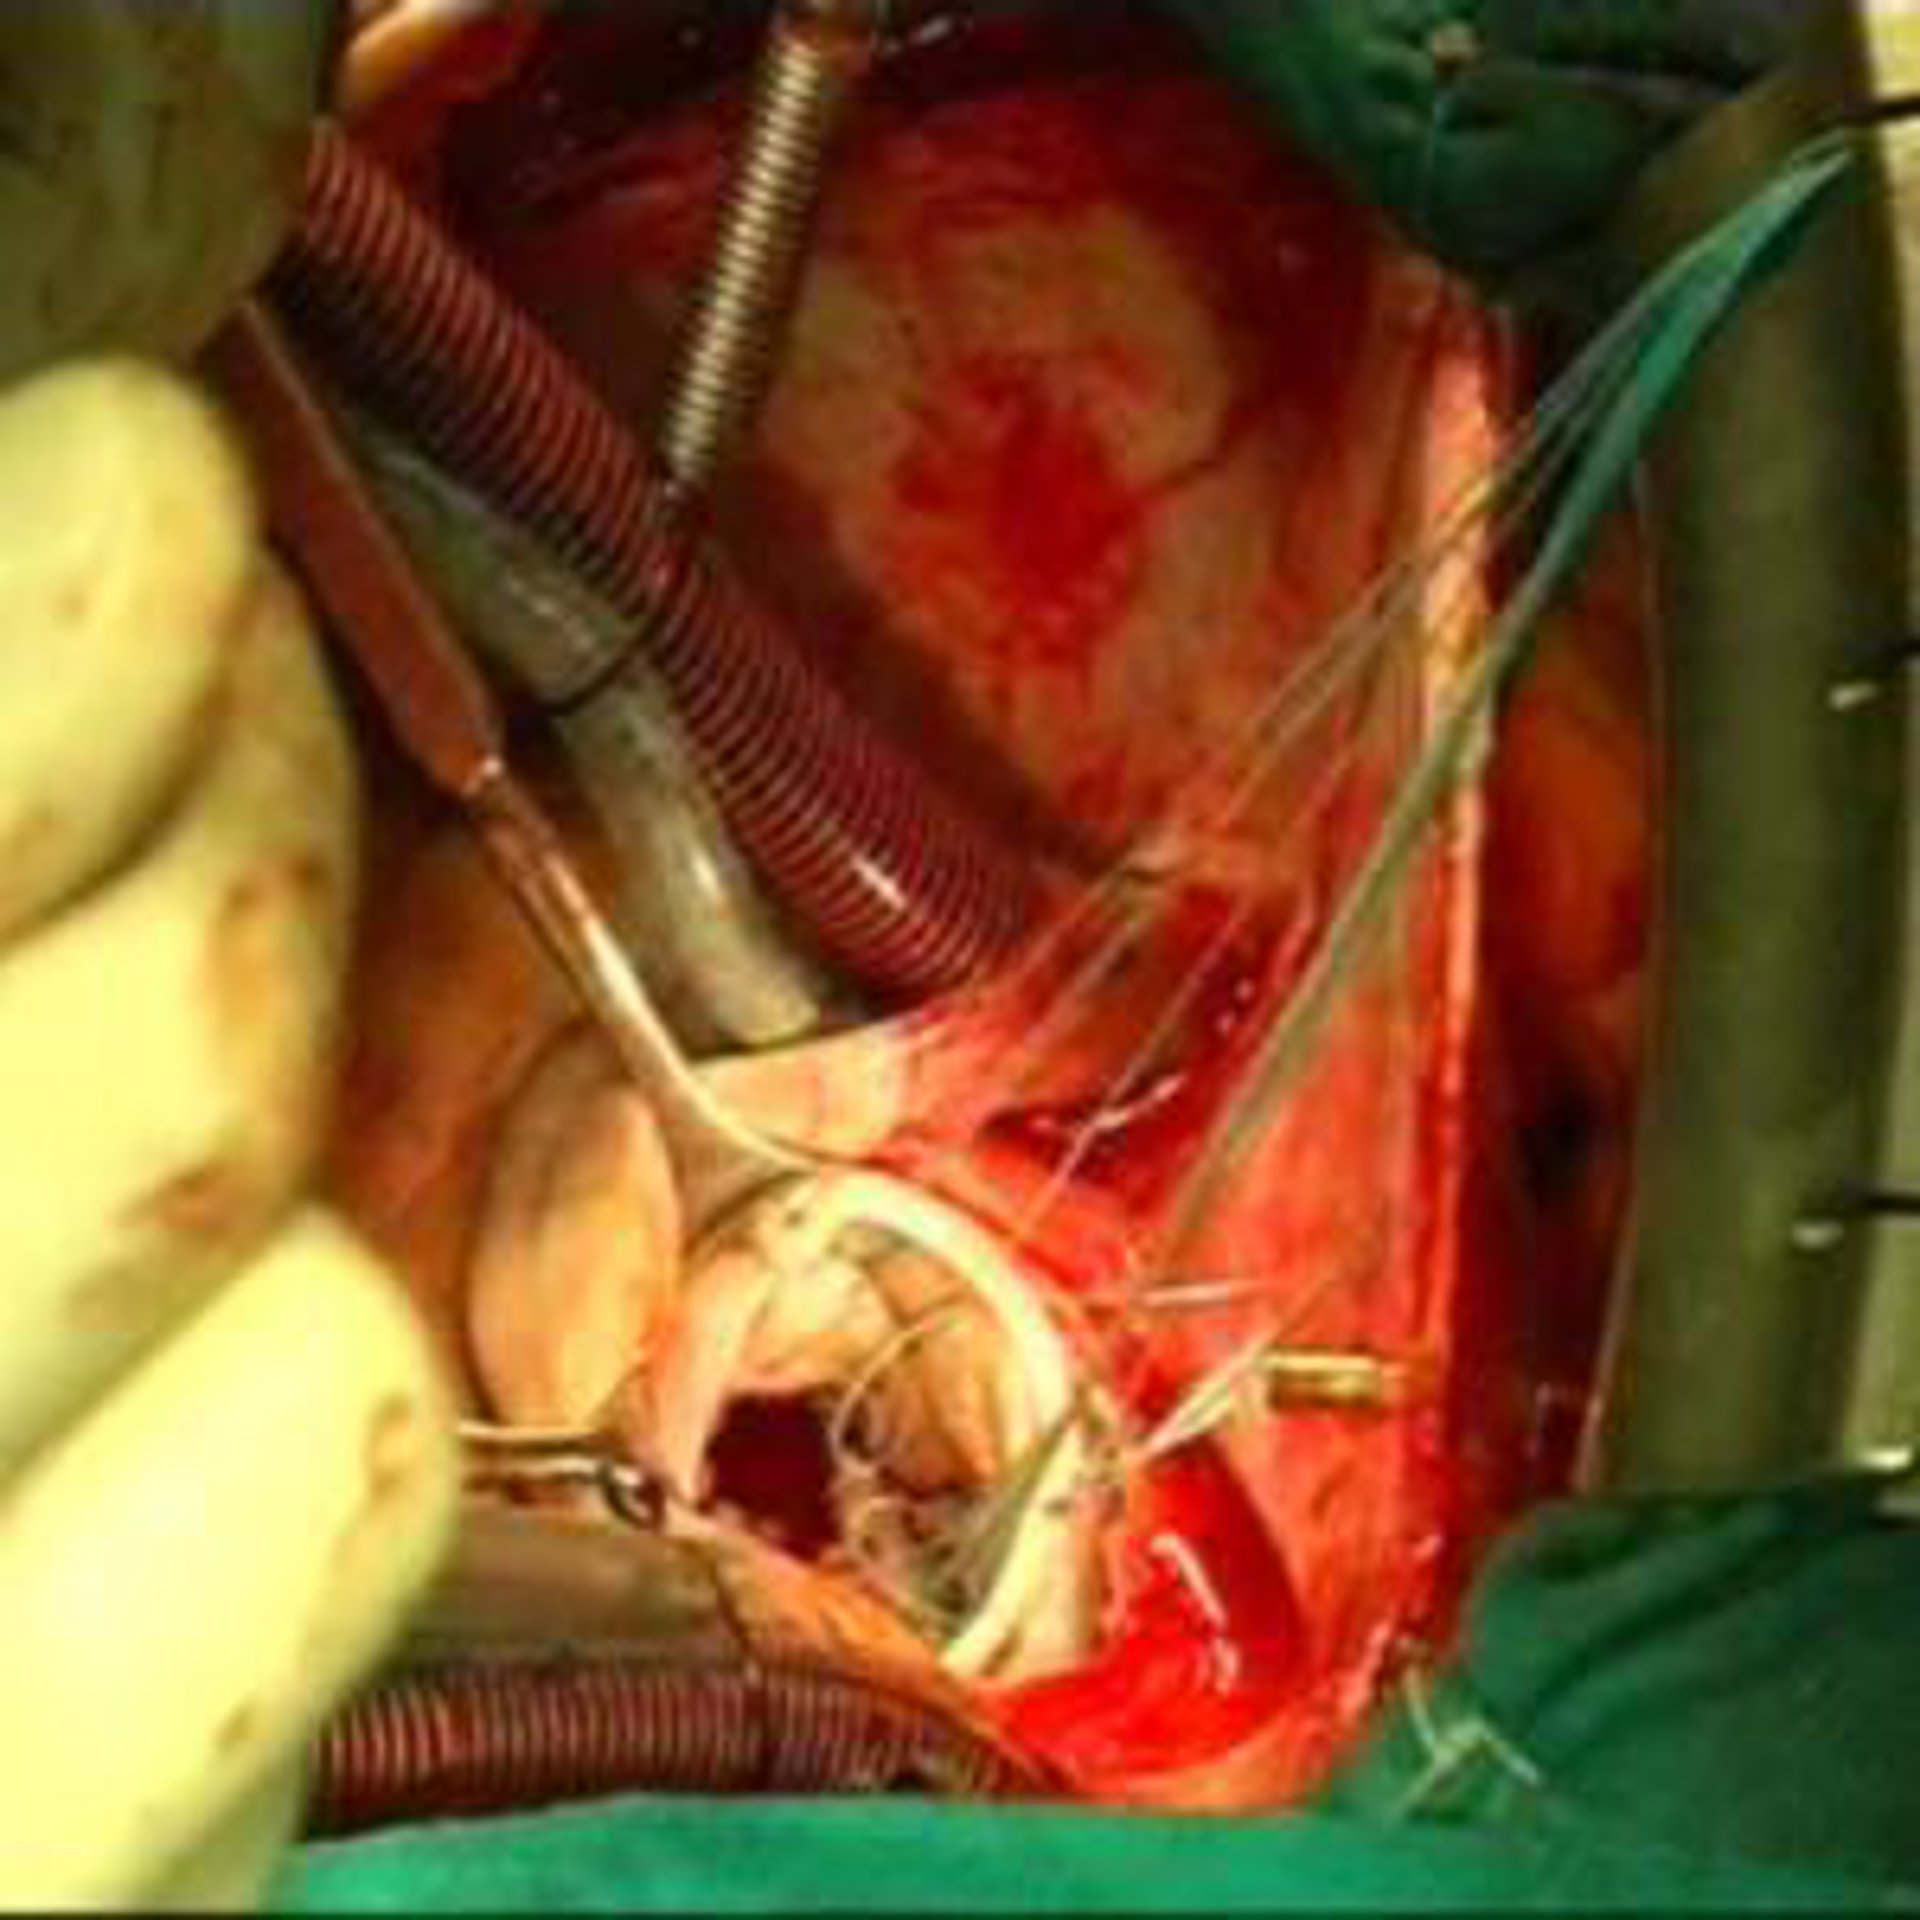

El Hospital Universitario Virgen Macarena de Sevilla ha realizado por primera vez en el mundo una punción guiada por ecoendoscopia de un tumor cardíaco, una técnica que ha permitido, por un lado, detectar este cáncer en fase primaria en una paciente de 41 años y, por otro, que los cirujanos hayan podido intervenirlo quirúrgicamente "sin ir a ciegas de lo que nos íbamos a encontrar", según destacó el jefe del Servicio de Cardiología, Carlos Infante.

Durante la exposición del caso, Infante explicó que dicha técnica diagnóstica, que se viene empleando para otros tejidos y órganos desde 1992, "aunque nunca para biopsiar un tumor cardíaco", permitió detectar en una fase primaria --temprana-- una masa tumoral originada en el pericardio "con una longitud de 17 centímetros, una anchura de ocho centímetros y un espesor máximo de cinco centímetros".

Añadió que tras la prueba endoscópica, que se realizó el pasado 30 de agosto y que duró apenas 10 minutos, la paciente permaneció 24 horas en Observación y monitorizada en la Unidad Coronaria, al objeto de controlar el comportamiento del corazón. Posteriormente, en concreto el 28 de septiembre, la paciente fue operada "mediante una cirugía rutinaria que no duró más de 45 minutos", prosiguió Infante.